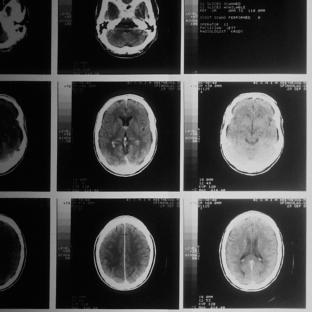

Focusing on data from trial participants receiving the highest monthly dose of aducanumab (10mg/kg, delivered via intravenous infusion), the researchers evaluated the incidence of amyloid-related imaging abnormalities, also known as ARIA. ARIA are detected using brain MRI scans, and can either manifest as accumulation of fluid deposits in the brain (known as ARIA-E) or as small brain bleeds (ARIA-H). Drugs such as aducanumab, which target and clear amyloid plaques, are known to cause side-effects that include ARIA.

Overall, 41% of people receiving the highest dose of aducanumab developed ARIA (425 of 1029 participants), compared to 10% of people receiving a placebo treatment. The majority of these ARIA cases were linked to fluid deposits in the brain (ARIA-E), and approximately 25% experienced mild symptoms linked to ARIA-E, including headache, dizziness or nausea. 1.4% of participants experienced more serious symptoms, requiring hospitalisation and/or causing long-term impairment. However, most cases of ARIA-E resolved within 16 weeks.

About 40% of participants with ARIA-E also had small brain bleeds (called ARIA-H). Participants who already had evidence of ARIA-H prior to commencing the trial were at double the risk of ARIA. In addition, participants with one or more ApoE4 alleles had a heightened risk of ARIA; 66% of participants with two ApoE4 alleles experienced ARIA, compared to 20% of participants with no ApoE4 alleles.